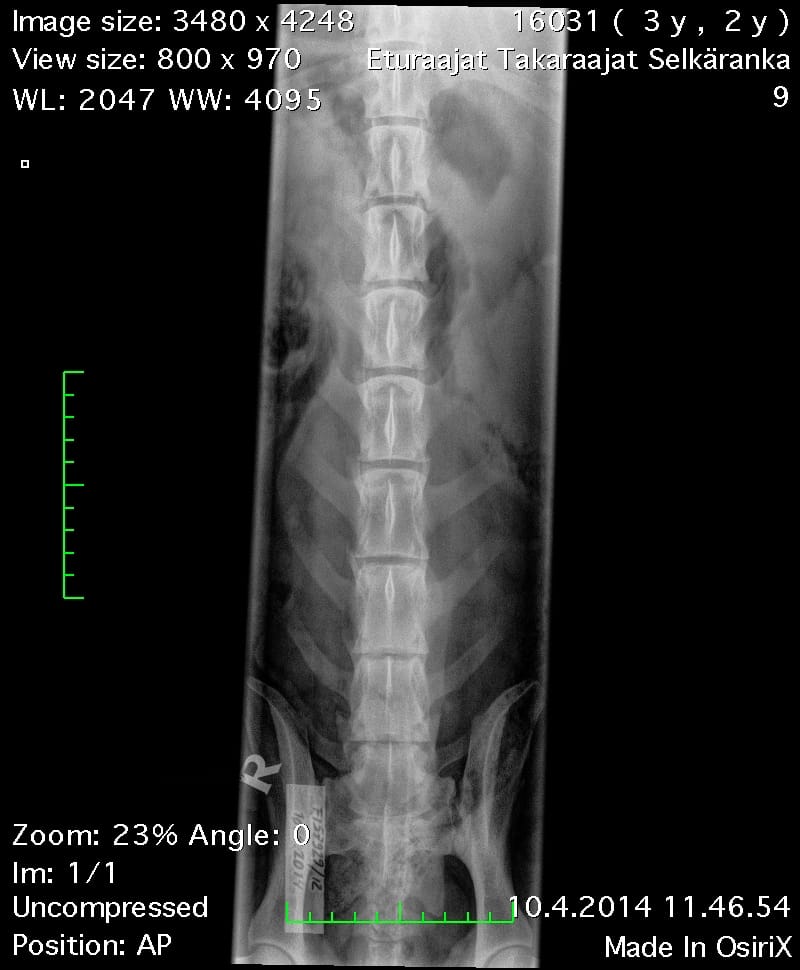

Oiva Lanneranka VD